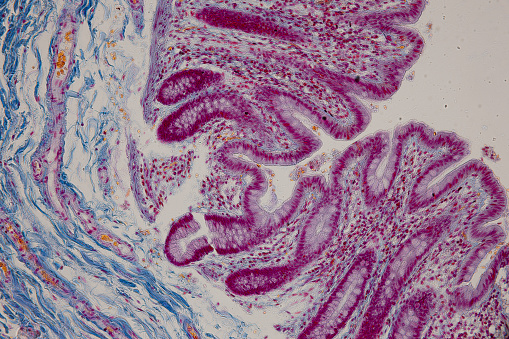

췌장은 소화 효소와 인슐린을 분비하여 소화와 혈당 조절에 중요한 역할을 합니다. 췌장에 문제가 생기면 소화 효소의 분비가 줄어들어 소화불량이 발생할 수 있습니다. 이 경우 복부 통증, 황달, 체중 감소 등의 증상이 동반될 수 있습니다. 특히 소화가 잘 되지 않고 체한 듯한 느낌이 자주 나타난다면 췌장암을 의심해볼 필요가 있습니다.

최근 통계에 따르면, 췌장암 환자는 매년 증가하고 있어 주의가 필요합니다.